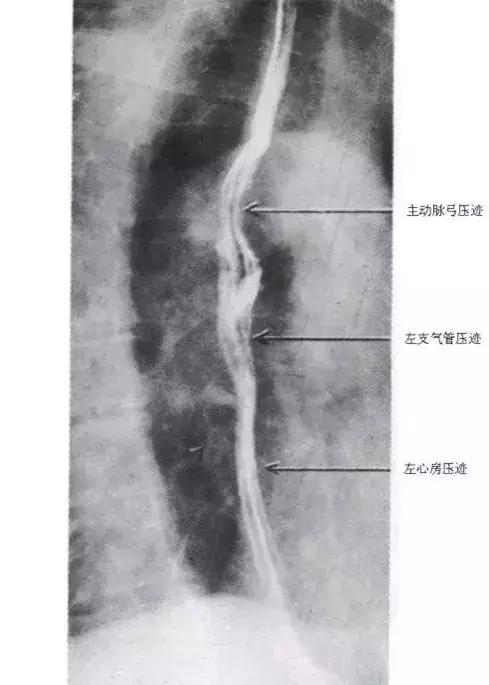

图23 食管X线像